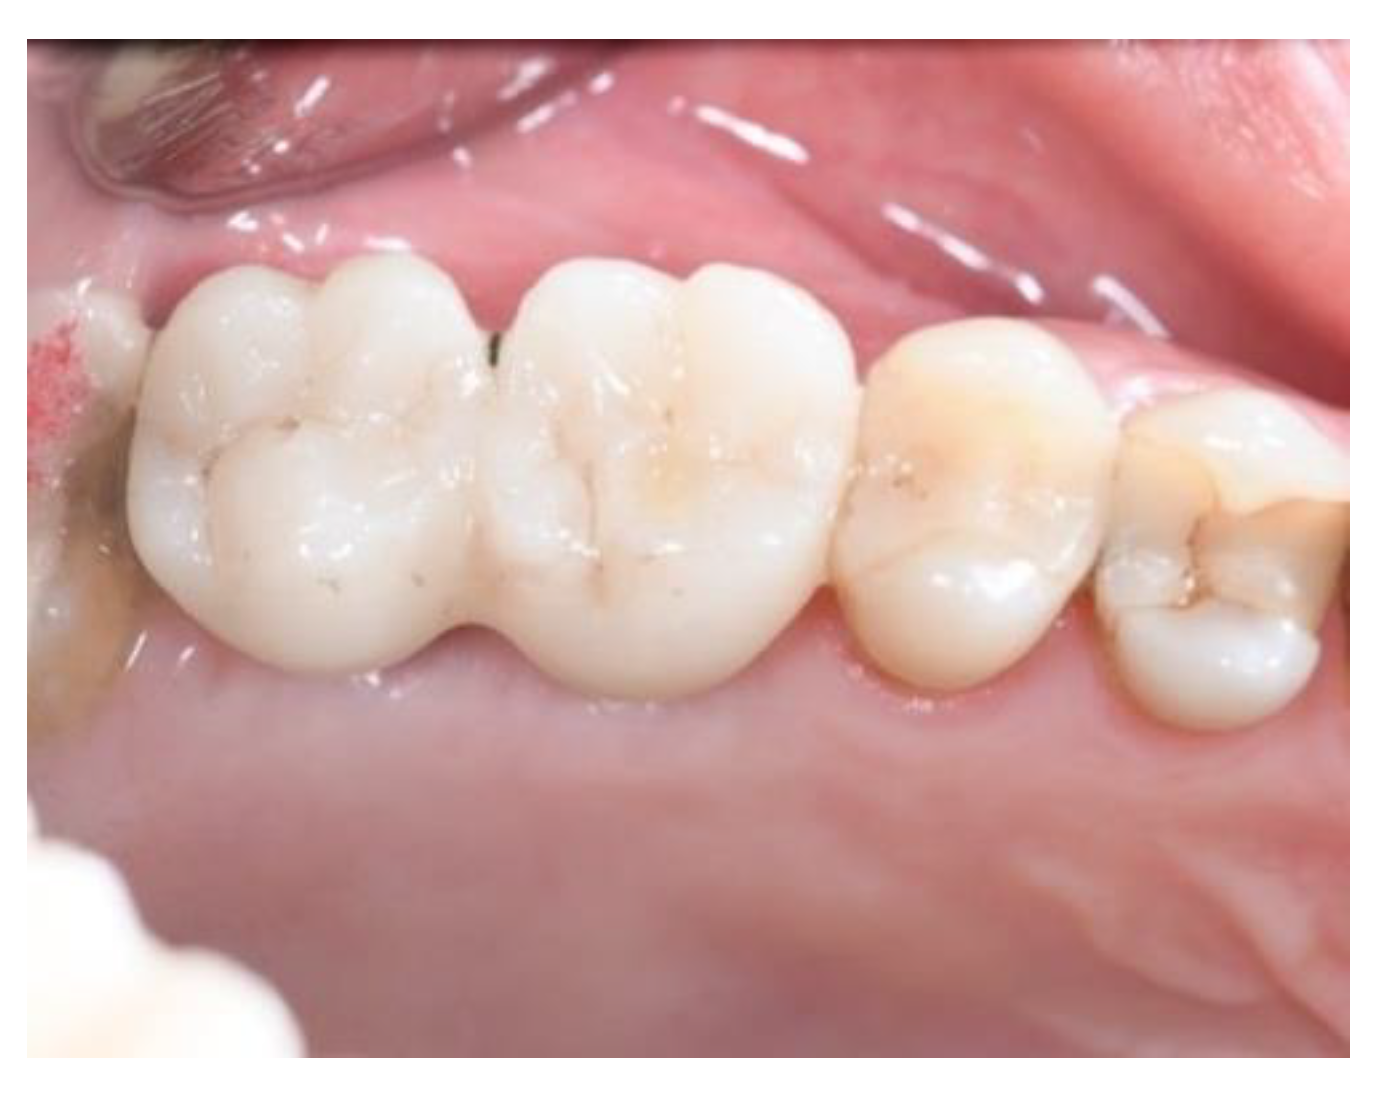

2.2. Follow-Up